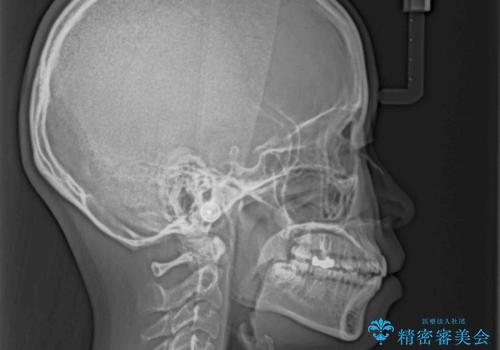

- 前歯の出っ歯と口元の閉じにくさを気にして来院された患者様です。

口元を積極的に引っ込めるために、上下左右の小臼歯4本を抜歯することとしました。

4本の歯を抜歯したことで、飛び出していた口元が引っ込み、横顔が大きく改善されました。